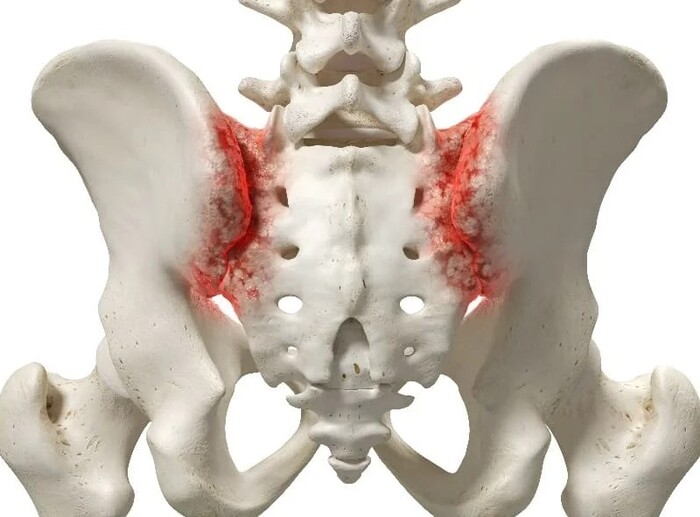

Сакроилиит — это воспаление одного или обоих крестцово-подвздошных суставов.

Остеоартроз крестцово-подвздошных суставов, часто вследствие травм, постоянных перегрузок.

Рентгенологические градации сакроилиита в соответствии с модифицированными Нью-Йоркскими критериями диагноза англизирующего спондилита:

0 стадия - Отсутствие изменений

1 стадия - Подозрение на наличие изменений (отсутствие конкретных изменений, смазанность субхондрального слоя).

2 стадия - Минимальные изменения (небольшие локальные области с эрозиями или склерозом, сужение или неравномерность суставной щели.)

3 стадия - Безусловные изменения (умеренный или значительный сакроилиит с эрозиями, склерозом, расширением, сужением щели или частичным анкилозом)

4 стадия - Далеко зашедшие изменения (полный анкилоз)